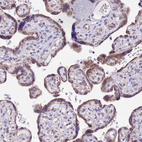

Immunohistochemical staining of human testis shows strong granular cytoplasmic positivity in a subset of cells in seminiferous ducts.